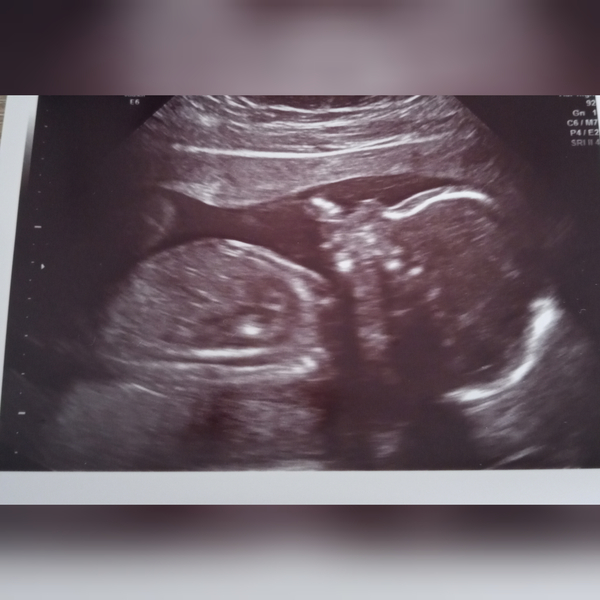

@Aria2015 great scan photo! My measurement was also 2.2mm which is apparently well within normal. My bloods came back within a week with very low risk which further put my mind at ease. So glad everything is looking good for you.

@Rachael321 your photo is so cute! Glad you have a happy wriggly baby. Halfway there now....

Hi ladies hope you are all keeping safe and well. I had my 20 week scan yesterday and it was hard having to go in on my own but it was so nice to see baby again and they made me feel at ease explaining everything to me,wearing the correct masks and gloves,adhering to the social distancing rule and she told me that everything had been wiped down and was before each patient so that was all good to hear. The sonographer was able to get all the measurements she needed (even though baby was being a wriggly little tinker and I had to do a bit of jumping up and down and swinging of the hips to get him to move for one of them) and all was as it should be which was such a relief and I got some nice pics to share with my partner,daughter and family.

Lovely scan @Bellsx glad all ok!

@Bellsx gorgeous photo, you must be relieved to have all those essential measurements done and dusted. Are you having a boy or a girl? Or are you waiting until the birth?

@Bellsx lovely scan picture, I'm so glad it went well, happy 20 weeks, congratulations on half way there!